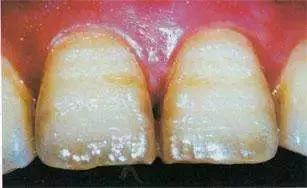

牙本质、牙釉质发育不全通常有这么几种表现

01牙面颜色有改变,呈棕色。

02临床表现是:有带状、或窝沟状凹陷。

03牙面可见平行横线。

04切缘变薄等等。

通常牙冠呈微黄色半透明,光照下呈现乳光,牙釉质易从牙本质表面分裂脱落使牙本质暴露,从而发生严重的咀嚼磨损,在乳牙列,全部牙冠可被磨损至龈缘,造成咀嚼食物、美观和语言等功能障碍。也有可能会牵连到恒牙,但乳牙列病情更为严重。